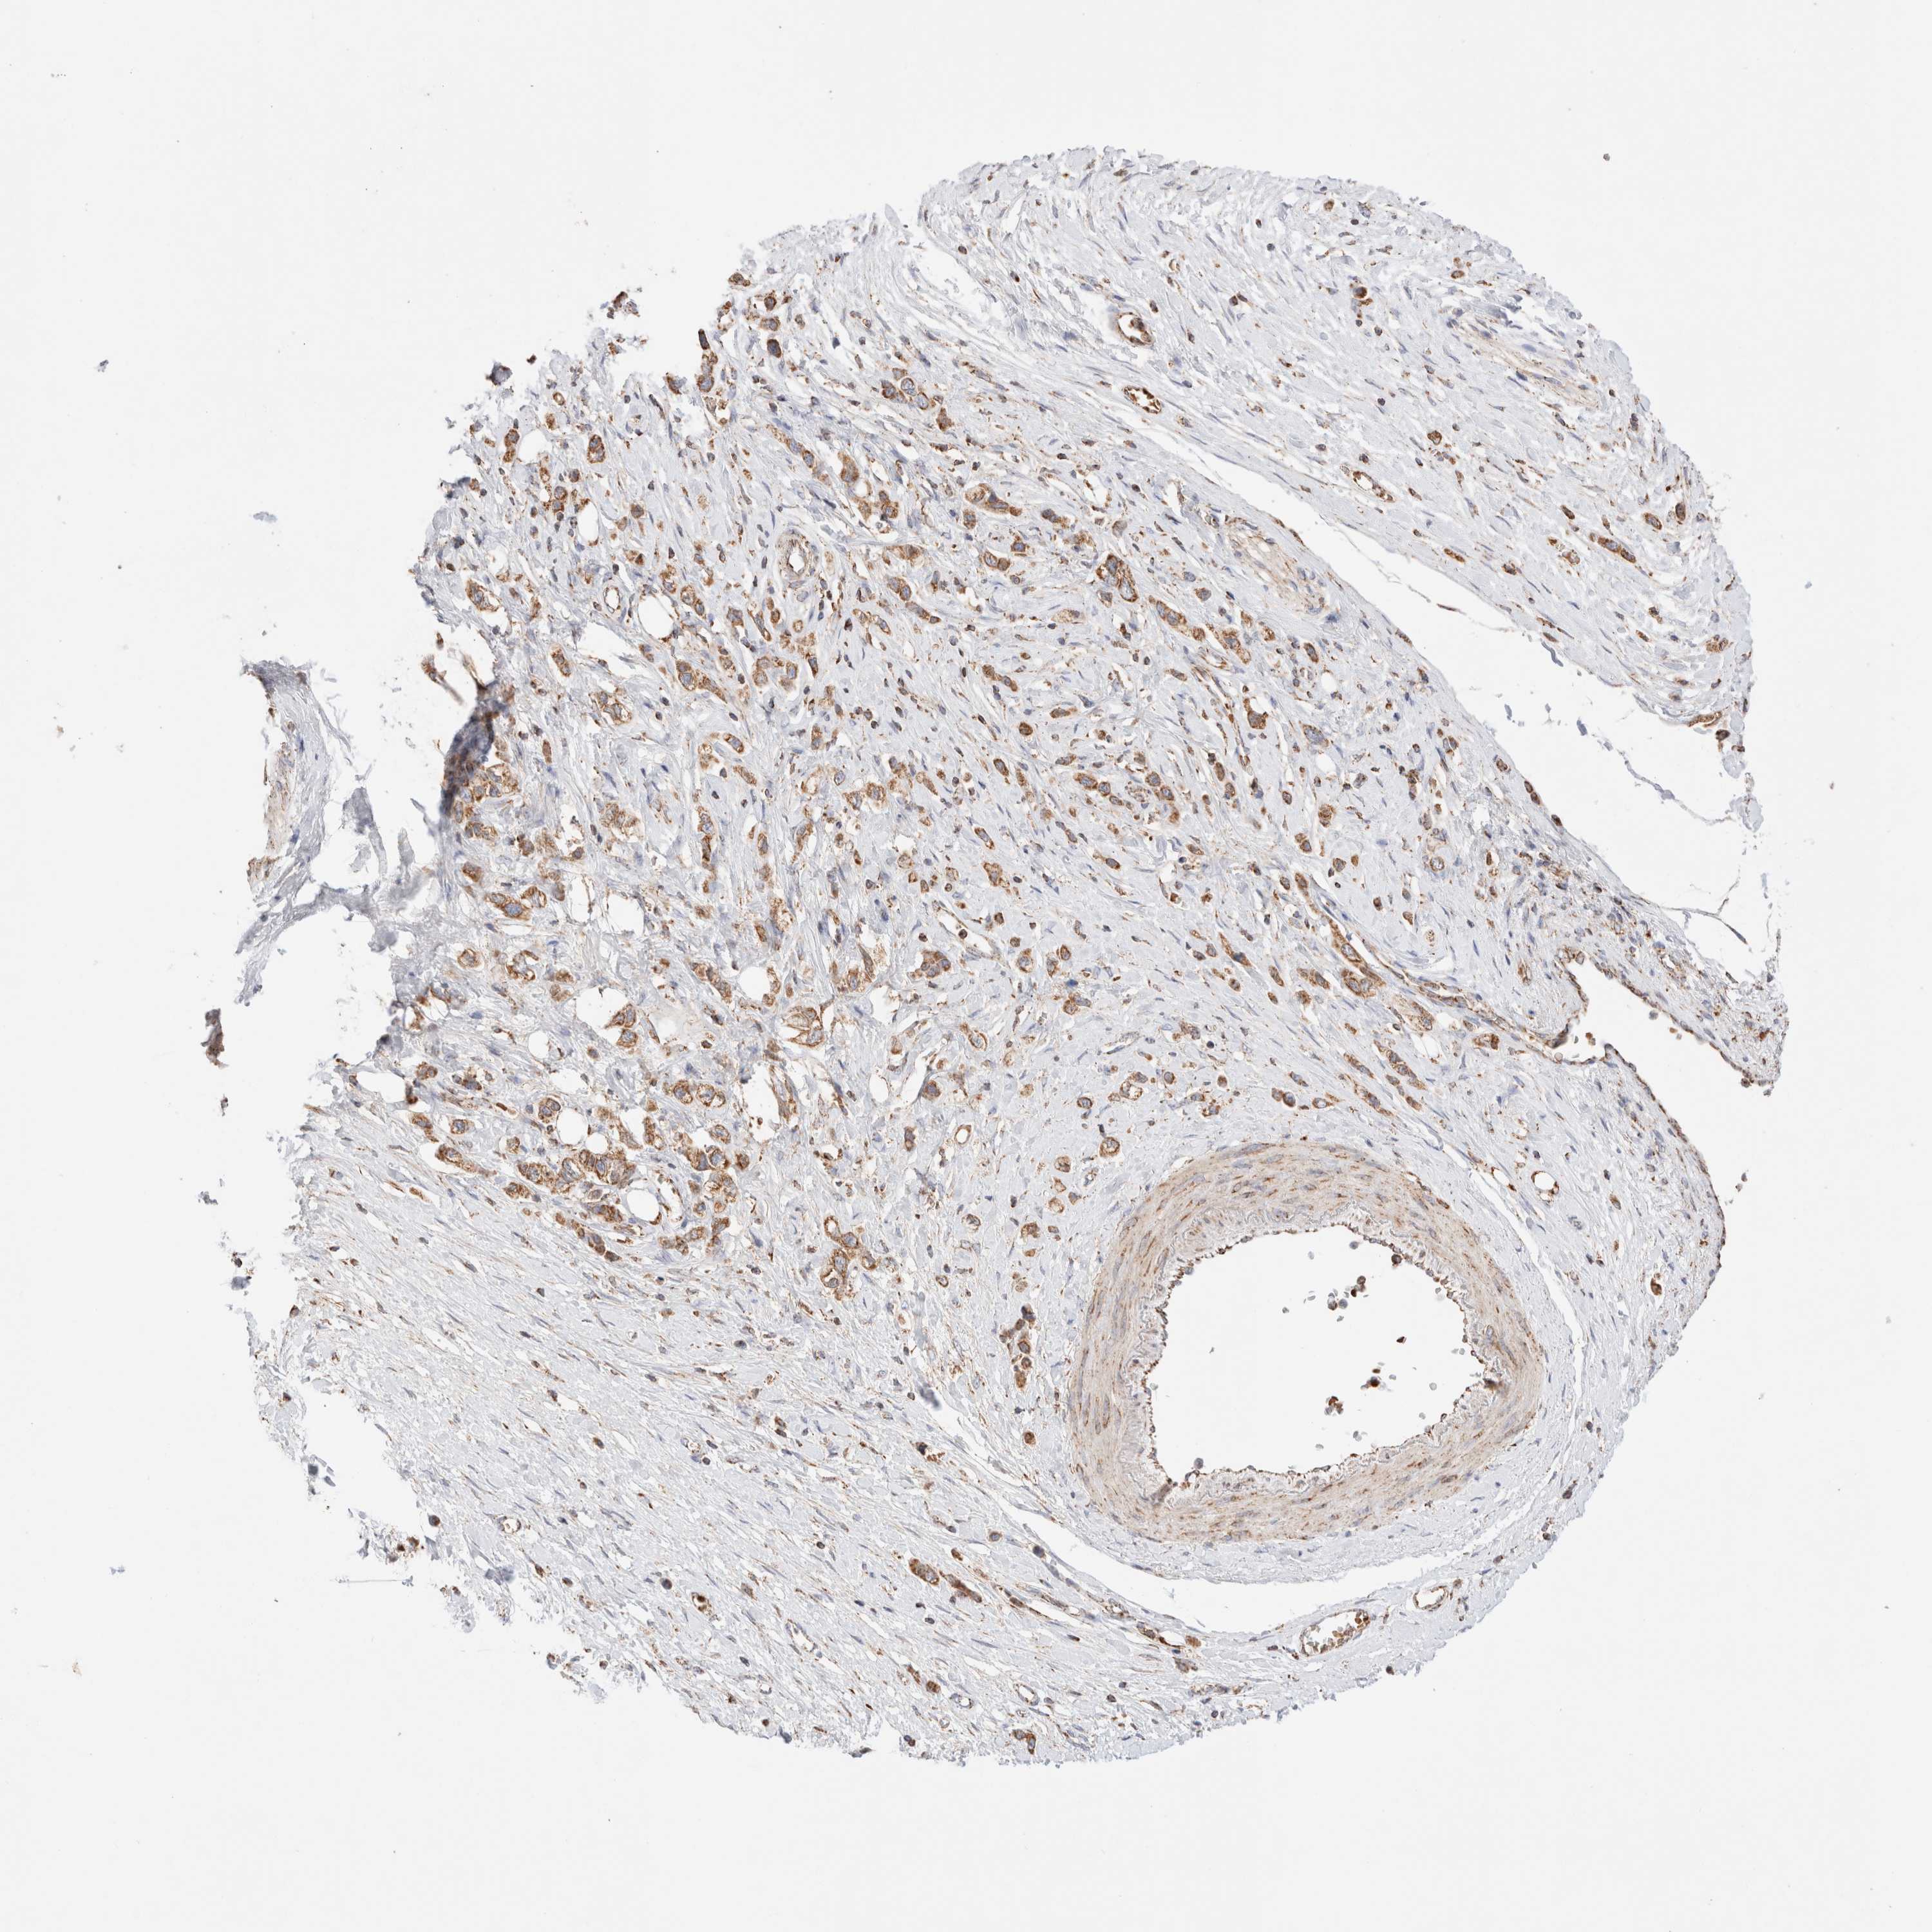

STOMACH CANCER - Protein expressioni

A mouse-over function shows sample information and annotation data. Click on an image to view it in a full screen mode. Samples can be filtered based on level of antibody staining by selecting one or several of the following categories: high, medium, low and not detected. The assay and annotation is described here.

Note that samples used for immunohistochemistry by the Human Protein Atlas do not correspond to samples in the TCGA dataset.

Antibody stainingi

Antibody staining in the annotated cell types in the current human tissue is reported as not detected, low, medium, or high, based on conventional immunohistochemistry profiling in selected tissues. This score is based on the combination of the staining intensity and fraction of stained cells.

Each image is clickable and will lead to virtual microscopy that enables deeper exploration of all samples and also displays staining intensity scores, fraction scores and subcellular localization as well as patient and tissue information for each sample.

Antibody HPA027019

Staining

High

Medium

Low

Not detected

Intensity

Strong

Moderate

Weak

Negative

Quantity

>75%

75%-25%

<25%

None

Location

Nuclear

Cytoplasmic/membranous

Cytoplasmic/membranous,nuclear

Adenocarcinoma, NOS